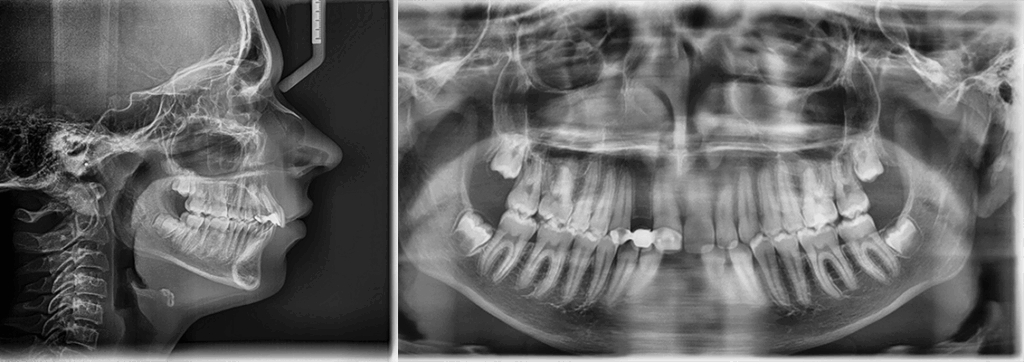

Skeletal Class II due to mandibular retrognathia, proclination of maxillary incisors, narrow arch creating a V-shaped arch, agenesis of 12, 31, 41, hyperdivergent facial pattern, moderate deep bite (2 mm), increased overjet (9 mm), asymmetric canine and molar Class II due to mandibular deviation to the left, maxillary midline deviation related to agenesis of 12, distal rotation of 35 and 45, and pronounced lower curve of Spee.

Labial incompetence, mouth breathing, tongue dysfunction

A monobloc appliance was prescribed to stimulate mandibular growth.